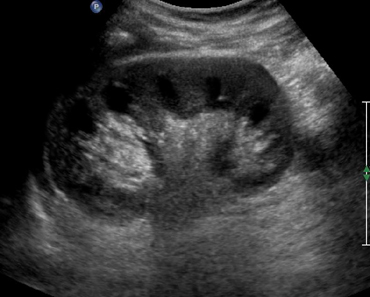

Повышенное газообразование часто является препятствием для полноценного проведения диагностики, поскольку скопившиеся газы мешают четкой визуализации органов. Жировая прослойка в области живота также мешает визуализация органов. В этом случае ультразвуковые волны не могут проникнуть вглубь тканей и отразить исследуемые органы.